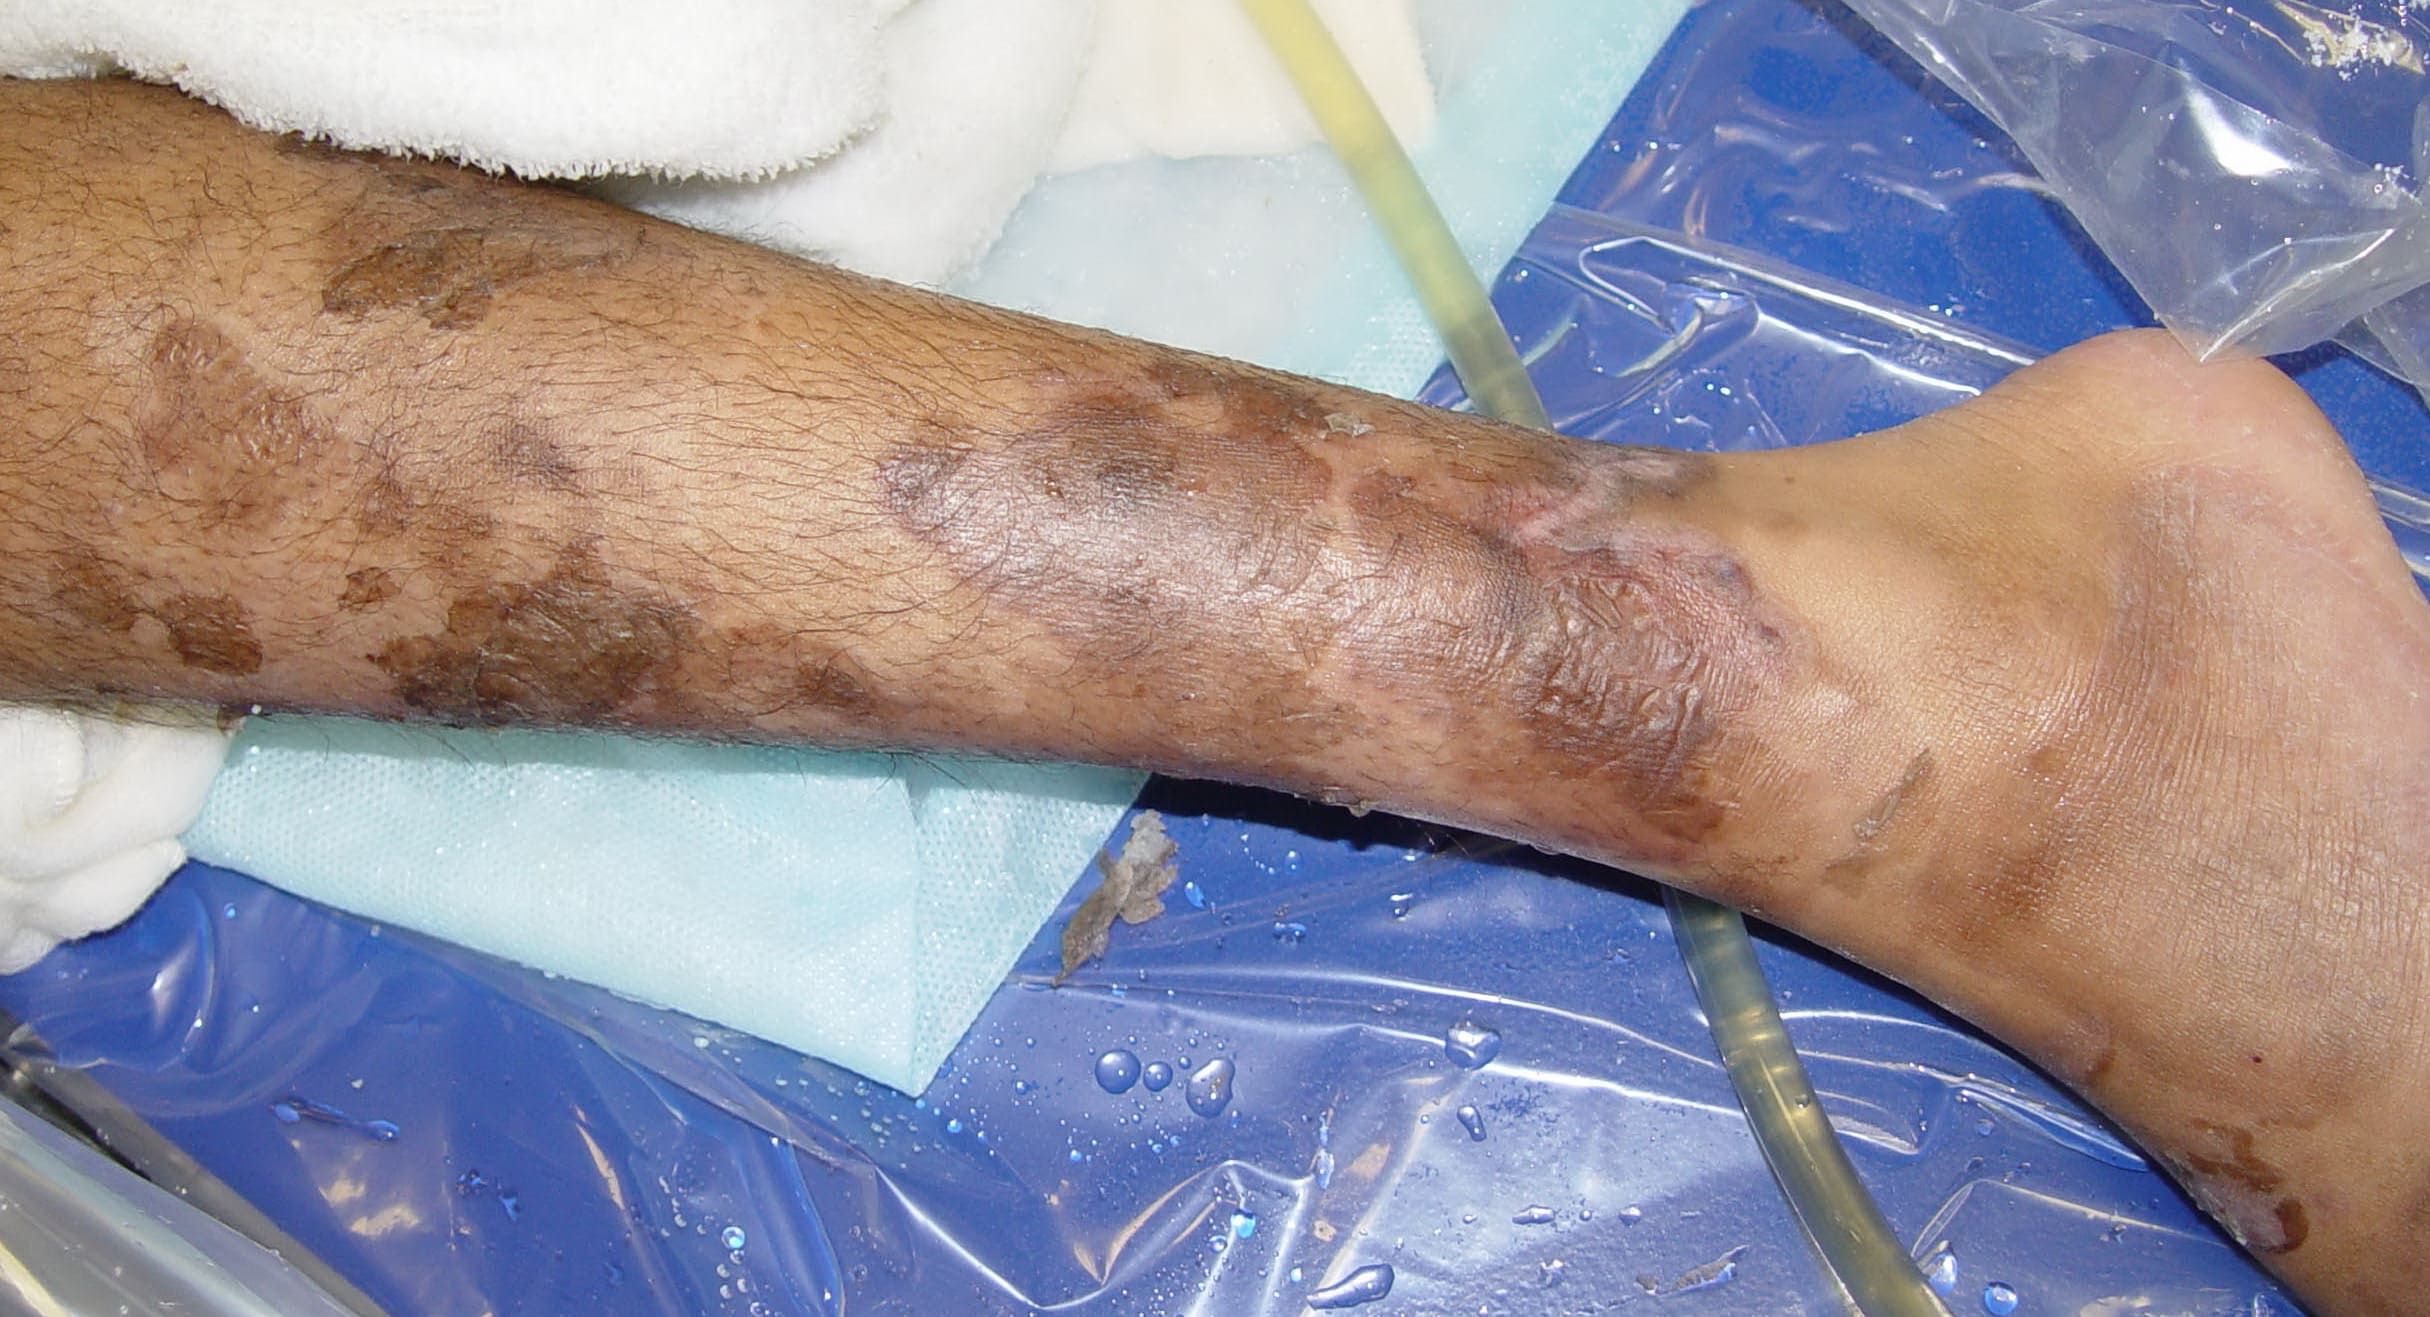

Pemphigis Vulgaris =الفقاع الشائع